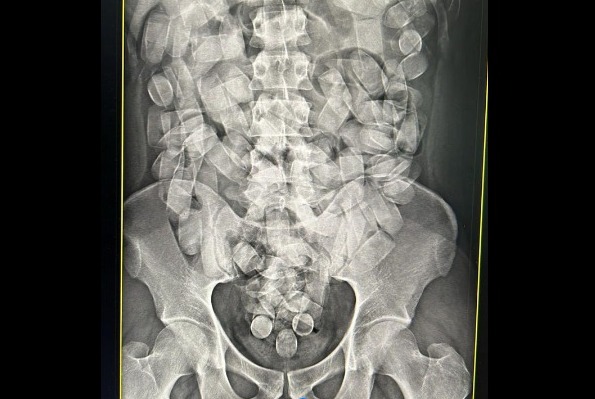

Homem é preso no aeroporto de Corumbá com 125 cápsulas de cocaína no estômago

No último domingo (19), policiais federais realizaram a prisão em flagrante de um homem enquanto tentava embarcar em um voo com destino a São Paulo.

Ele estava transportando cocaína em cápsulas no estômago. O caso ocorreu no aeroporto de Corumbá. O passageiro estava com 125 cápsulas ingeridas de cocaína. Segundo o registro policial, esta é a segunda prisão nesta semana no mesmo aeroporto realizada pela Polícia Federal.